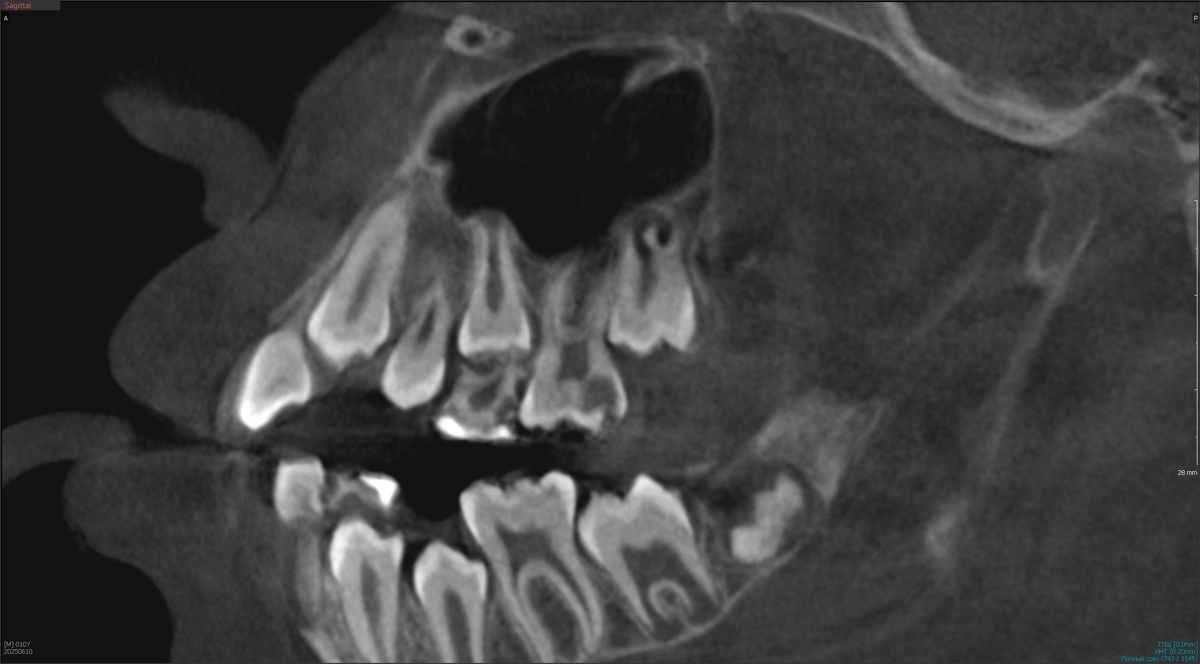

На КТ всё выглядит плохо:

Видите, насколько тонкая полоска твёрдых тканей отделяет пульпу от краха? Приблизим: